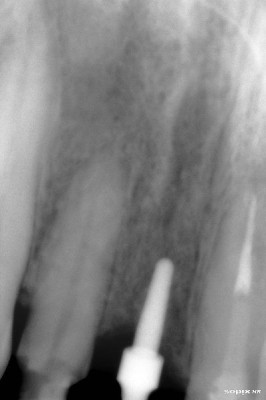

Radiografía inicial